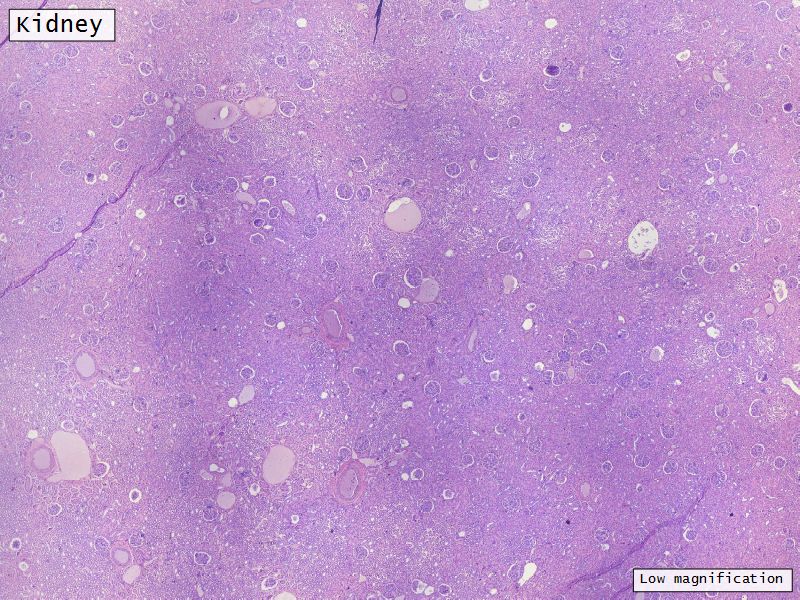

Appearance

• Cortex

• Renal corpuscles

• Convoluted tubules

• Medulla

• Loops of Henle

• Collecting tubules

Kidney lobule

• Group of neprons

• Open into branches

• Same collecting duct

• Not clearly demarcated

• Interlobular arteries/veins